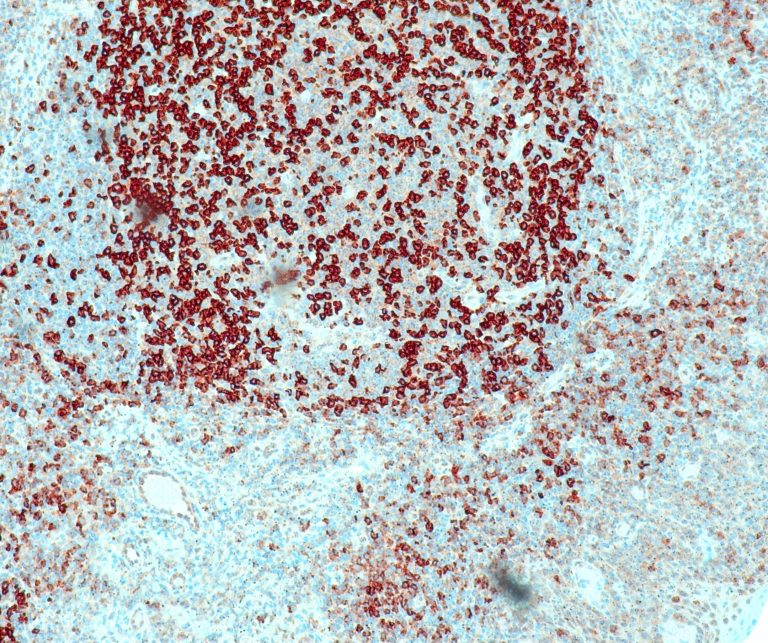

Hematopathology